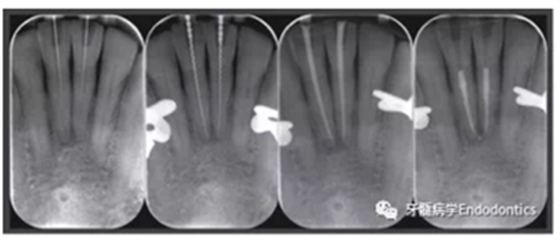

在患者下頜牙上試戴導(dǎo)板(帶有專(zhuān)門(mén)制作的金屬袖,steco-system-technik GmbH & Co. KG, Hamburg, Germany) ,判斷是否合適(圖7)。通過(guò)導(dǎo)板可以定位根管入路點(diǎn),并微創(chuàng)去除牙釉質(zhì),直到牙本質(zhì)暴露。鉆針轉(zhuǎn)速設(shè)定為10000RPM,上下提拉鉆頭獲得根管根尖1/3的入路(圖8)。當(dāng)鉆針柄接觸導(dǎo)板上的金屬袖時(shí),鉆針尖端到達(dá)目標(biāo)位點(diǎn)。整個(gè)根尖入路的制備過(guò)程耗時(shí)約10分鐘。圖9展示了微創(chuàng)預(yù)備的根管入路。然后進(jìn)行常規(guī)的根管治療。用1%的次氯酸鈉沖洗根管,單支往返銼(R25, VDW, Munich, Germany)預(yù)備根管,超聲蕩洗,干燥根管后用氫氧化鈣(Ultracal XS, Ultradent Products Inc, South Jordan, UT, USA) 封藥,暫封(CavitTM, 3 M ESPE) 。兩周后,患牙均無(wú)叩痛,使用熱牙膠垂直加壓技術(shù)和環(huán)氧樹(shù)脂糊劑(AH Plus, De Trey, Konstanz, Germany)充填根管。圖10為根管治療過(guò)程中拍攝的x線(xiàn)片。髓腔清理后,使用復(fù)合樹(shù)脂(Filtek Supreme XTE, 3 M ESPE, Seefeld,Germany) 和多步法粘接劑(Optibond FL, Kerr, Orange, CA, USA).充填。

圖10.根管治療過(guò)程中拍攝的X線(xiàn)片。(a)微創(chuàng)根管入路制備完成拍攝的定位片,(b)根管長(zhǎng)度測(cè)量,(c)試主尖片,(d)去除冠方根充填物后的最終根充效果。